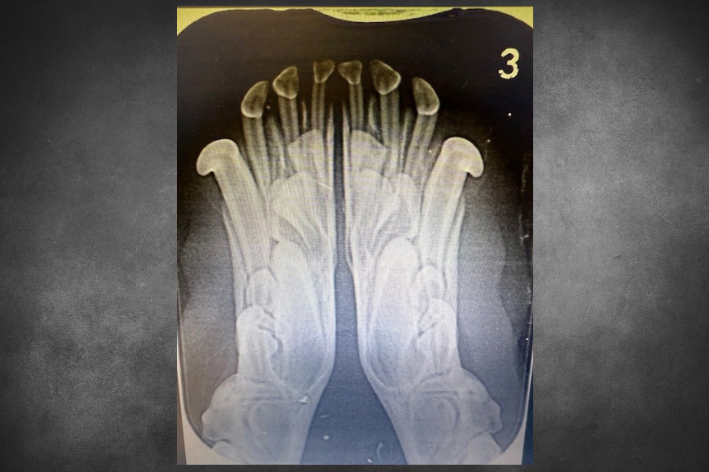

Photo: Luna’s Xray (© Coquet Vets, 2025)

We recently treated a 13-week-old small cross breed named Luna, who came to us with Lingually Displaced Deciduous Canines (LDDC). LDDC is a genetic condition where a dog’s lower deciduous canines (baby teeth) are growing into the hard palate (top of the mouth). The teeth are growing too far towards the tongue (lingually). LDDC occurs in dogs due to a combination of genetic factors and the retention of baby teeth.

Luna presented as a classic case of LDDC, as the small cross breed could not close their mouth without these teeth contacting the soft tissues of the upper hard palate. This was causing some discomfort, and as teeth growing into the hard palate can be painful for a puppy, it was agreed with the owner to remove Luna’s deciduous teeth.